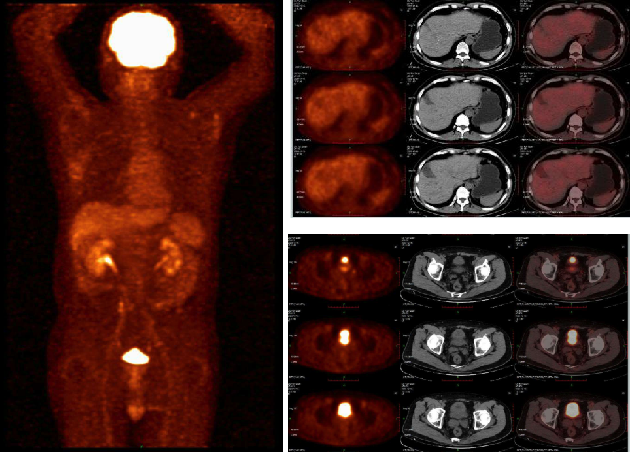

2020-12-16 18 F-FDG PET/CT提示:直肠壁未见确切异常增厚及糖代谢异常增高,盆腹部淋巴结未见增大及糖代谢异常增高;肝囊肿。